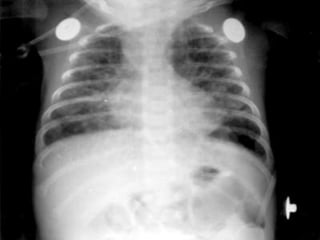

HALLAZGOS RADIOGRÁFICOS:

• Disminución del volumen

• Opacificacion difusa con campos pulmonares con

moteados en vidrio esmerilado (Infiltrado

Reticulonodular difuso)

• Presencia broncograma aéreo

ENFERMEDAD DE LAMEMBRANA HIALINA HALLAZGOS RADIOGRÁFICOS: • Disminución del volumen • Opacificacion difusa con campos pulmonares con moteados en vidrio esmerilado (Infiltrado Reticulonodular difuso) • Presencia broncograma aéreo